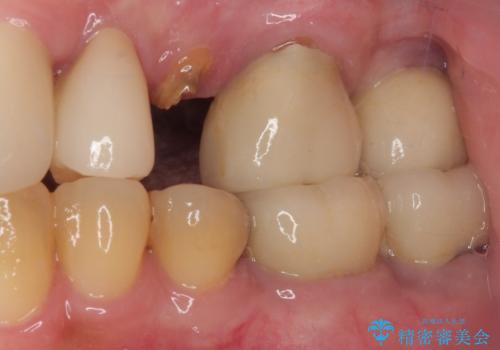

破折によりクラウンの外れてしまった奥歯 抜歯即時埋入で短期間インプラント治療

歯肉や歯槽骨の状態は良好であったため、抜歯即時埋入インプラントによる補綴治療を行うこととしました。

最小の来院回数で短期間で治療を終えることができました。